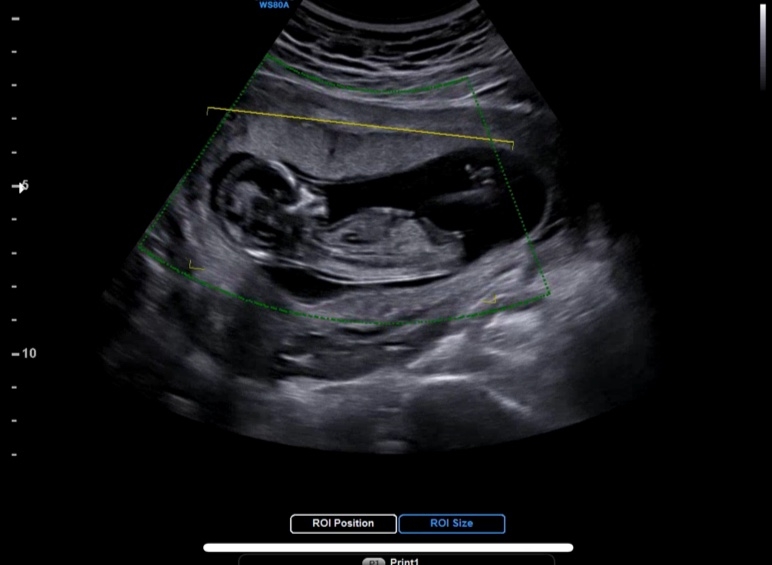

각도법 고수님들 조언부탁드립니다

아들인가요 딸인가요??

딸 같아용